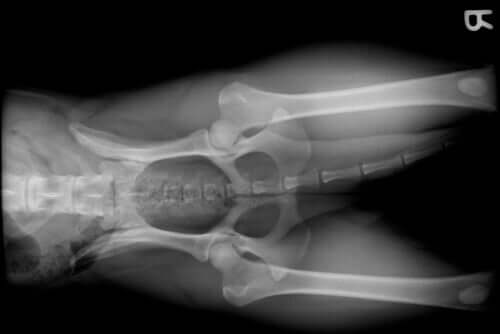

L’une des nombreuses raisons pour lesquelles un chien se retrouve chez le vétérinaire est l’apparition de pathologies articulaires. Une personne remarque généralement ce problème chez son chien avec l’apparition d’une boiterie et, parfois, d’une douleur aiguë.

Les problèmes articulaires chez un chien peuvent apparaître pour de nombreuses raisons, comme par exemple :

- La race : certaines races de chien, comme le berger allemand, développent souvent une dysplasie de la hanche. Et, au contraire, des races comme le golden retriever, le rottweiler ou le doberman, en raison de leur grande taille et de leur croissance rapide, souffrent généralement d’une dysplasie de l’épaule ou du coude

- L’âge avancé : comme les autres mammifères, y compris l’être humain, des pathologies liées à la vieillesse apparaissent chez les chiens. Nous parlons ici de la maladie articulaire dégénérative du chien

- Les problèmes de croissance : la période de croissance d’un chien est un moment délicat, comme chez d’autres espèces. Des carences alimentaires, des problèmes hormonaux ou même la race peuvent provoquer des dommages au niveau des articulations

- Des fractures impliquant les articulations

- Une rupture du ligament croisé antérieur : à cause d’efforts soutenus, d’un excès d’exercice ou de l’appartenance à une petite race, le ligament croisé antérieur peut se briser. Ceci dérive vers de sérieux problèmes d’articulation

- L’obésité : en plus de diminuer fortement la qualité de vie de notre animal, l’obésité provoque, entre autres choses, une surcharge des articulations. Ceci peut conduire à de graves problèmes

- L’arthrose

- L’arthrite